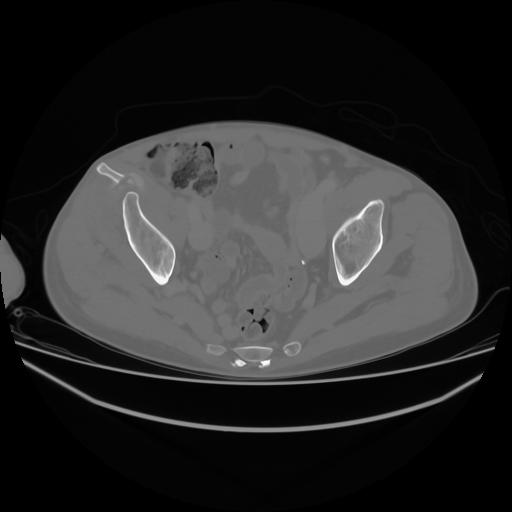

4 CUERPO,CE,Axial,3.0,CUERPO,,